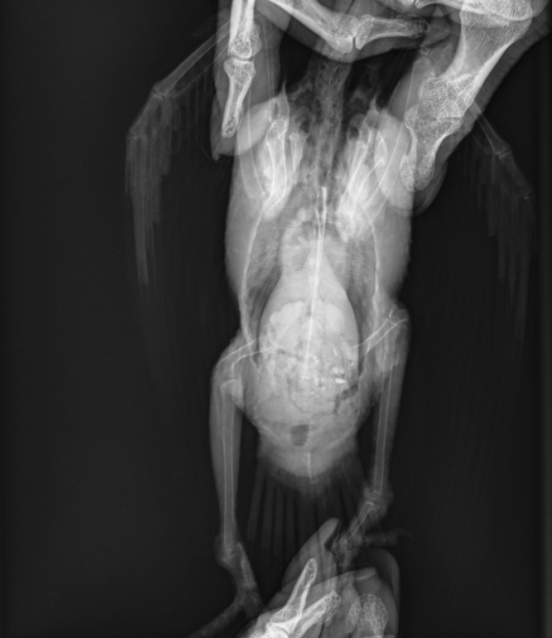

Уже приехав домой и посмотрев рентген, я увидела, что раскладка сделана странно, да и то, что наш птенец совсем не мог ходить даже после обезболивающего, меня беспокоило. Поэтому на следующий день я всё-таки отвезла его на приём к одной из наших постоянных докторов. Та сделала новый рентген и, судя по всему, провела мини-консилиум в мессенджере, после чего сказала: да, похоже, что есть переломы обеих голеней по типу "зелёной ветки". Поясню: это когда кость повреждена с одной стороны, а вторая сторона осталась целой - как если ломаешь молодую, ещё гибкую ветку дерева, она надламывается, но не разделяется на два отдельных фрагмента. Сказала, это частый вид травм у молодняка, связанный с тем, что масса тела прибывает быстрее, чем крепнет костно-связочный аппарат, и такая травма может возникнуть практически из ничего. Я, в свою очередь, грешу на то, что этим птенцам давала кальций другой фирмы, более дешёвый - может, он был некачественный...

Такие переломы непросто увидеть на снимках, и точная раскладка имеет большое значение. Обычно для рентгеновских снимков птиц раскладывают в четыре руки. Первая врач делала это в одиночку - она работала без ассистента. И конечно же, раскладка получилась кривая. Думаю, она зря никого не позвала помочь. Мне доводилось помогать с раскладкой на рентгене, но она меня видела впервые, и недоверие ко мне как к потенциальному помощнику тоже можно понять.

Врач сказала, лангеты накладывать ему нет смысла - такие переломы стабильны, а он слишком маленький. Но ограничение подвижности - обязательно, на три недели, контрольный рентген через две недели. Пришли к решению, что жить он будет пока в переноске. Летать было на все три недели запрещено, т.к. нормально приземляться он не мог, и при неудачной посадке был риск усугубить травму.